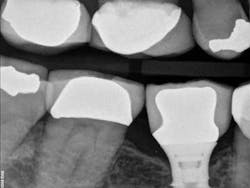

Fig. 2: X-ray of crown try-in two weeks after initial visit. No cement had been used at this point in the appointment. However, if you look at the distal of the implant, there is residual cement. This means that the cement came from the cementation of the temporary.

Fig. 3: Final X-ray after cementation. Temporary cement on the distal has been removed.